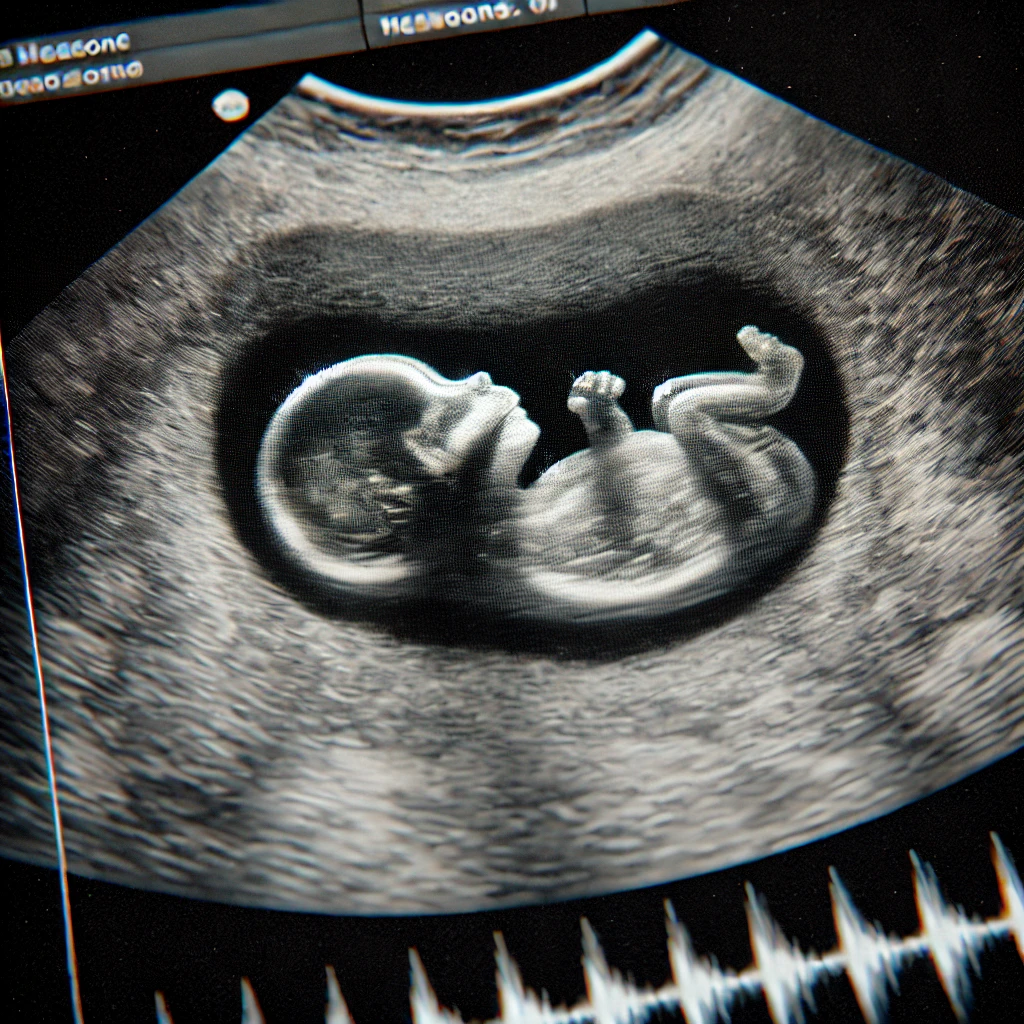

Cette formation s'adresse aux sages-femmes qui pratiquent le suivi de grossesse et qui ne sont pas échographistes

Souvent, en pratique, le professionnel qui effectue le suivi médical de la grossesse n'est pas l'opérateur des échographies. C'est pourquoi il est indispensable que chaque professionnel qui suit une grossesse ait les compétences pour lire et interpréter des images ou un compte-rendu échograhiques.

Cette formation apportera aux sages-femmes les outils nécessaires à l'analyse et l'utilisation de l'examen échographique pour le suivi de la grossesse et l'information des patientes.

Elle reprendra notamment les bases de l’échographie, ainsi que la législation en vigueur et les recommandations de la CNEOF. La seconde partie abordera les 3 échographies obligatoires de la grossesse et les différents éléments qui s’y rapportent, puis les stagiaires auront l’occasion d’aborder les situations particulières abordables par l’échographie comme la bonne évolution d’une grossesse, l’évaluation du bien-être fœtal, et pour celles et ceux qui pratiquent la gynécologie, la surveillance de DIU est évoquée.

A partir de cas cliniques et d’images échographiques, la formatrice amènera toute son expertise et illustrera les différents thèmes, abordés de façon concrète et dynamique.